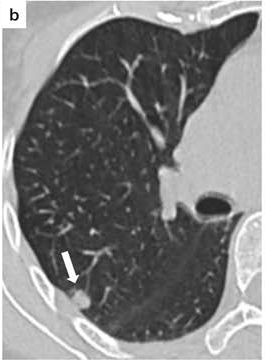

COVID19-CT dataset [51]: The dataset consists of a total of 746 CT images. There are 349 CT images of patients with COVID-19 and 397 CT images showing Non-COVID-19, but other pulmonary diseases. The positive CT images were collected from preprints about COVID-19 on medRxiv and bioRxiv, and they feature various manifestations of COVID-19. Since the CT images were taken from different sources, they have varying sizes between and . Figure 8 shows example CT images from the COVID19-CT dataset.

On the COVID19-CT dataset, the overall performance with respect to all evaluation metrics is inferior to that on the SARS-CoV-2 dataset. This can be attributed to the cross-source heterogeneity of the CT images in the dataset. The Non-COVID-19 CT images were taken from different sources and show diverse findings which pose difficulty to distinguish between COVID-19 and other findings associated with lung diseases due to the potential overlap of visual manifestations (see Figure 8). Another reason is that, the CT images in the COVID19-CT dataset show strong variations in contrast, variable spatial resolution and other visual characteristics, which could affect the model’s ability to extract more discriminative and generalizable features.

In a similar way, we consider classifying the test CT scans from the COVID-19 dataset by the DenseNet169 model and highlight the important regions considered for predictions. We present the original CT images and their localization maps in Figure 13. We can also see that our model is capable to detect the COVID-19 related regions as marked (small square in some images) by expert radiologists.

Figure 16 shows various CT scans where only one lung is visible. The CT scans are also extracted from the paper [58] and show different CT manifestations of COVID-19 pneumonia marked by red squares. The InceptionV3 model is capable to classify them correctly as COVID-19, although it is trained on CT scans where the entire lung is visible. Intriguingly, when applying Grad-CAM we can see that all regions of abnormalities are accurately localized. This also proves the potential of our model to detect COVID-19 abnormalities in CT images outside the dataset used for training.